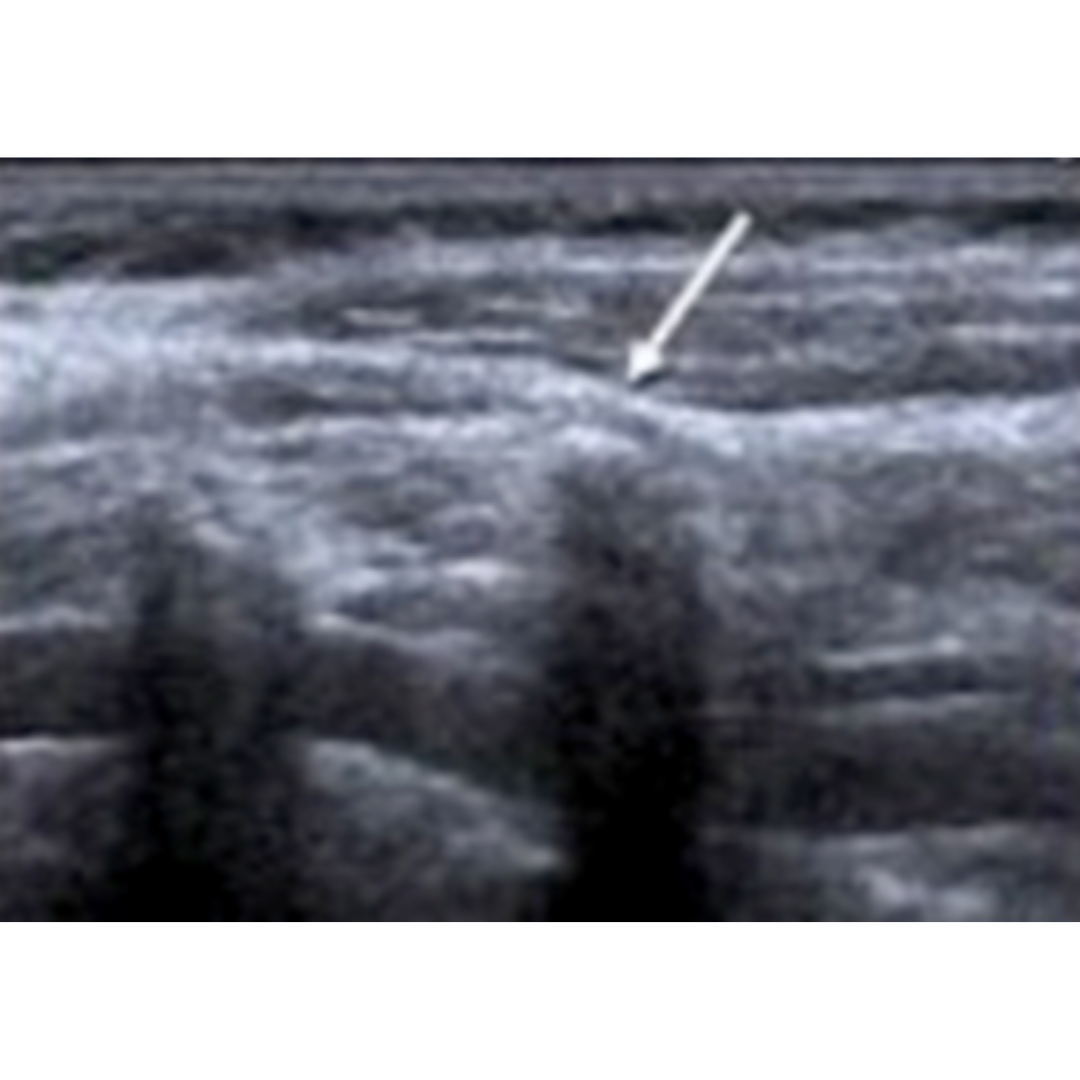

Figura 1. Corte longitudinal del lecho tiroideo, cambios post quirúrgicos normales recientes en el lecho tiroideo donde se observa un aumento de ecogenicidad de hipodermis, engrosamiento dérmico, cambios a nivel profundo con dificultad para observar planos debido al edema.